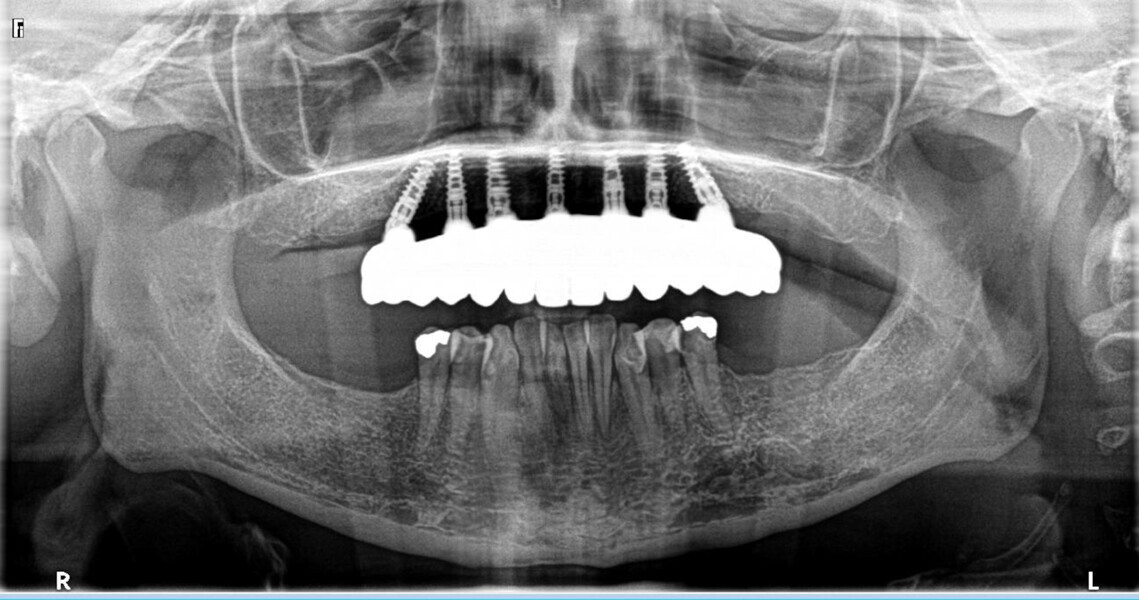

A CBCT scan and panoramic radiograph using the CS 8100 3D (Carestream Dental; Fig. 3) were taken to accurately capture the information needed to properly plan the treatment for this case that would ensure the most ideal outcome, especially since the patient had discussed how unhappy she was with her existing gummy smile. Using the CS 3D imaging software (Carestream Dental), dental implants were virtually planned in key positions to biomechanically support a full-arch fixed hybrid restoration in the maxillary arch (Fig. 4).

Fig. 3: Pre-op panoramic radiograph.

Fig. 4: Planning with the CS 8100 3D (Carestream Dental).